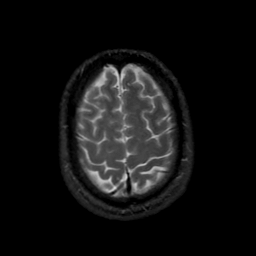

MR Study #18, July 21, 1991 -- Slice #42